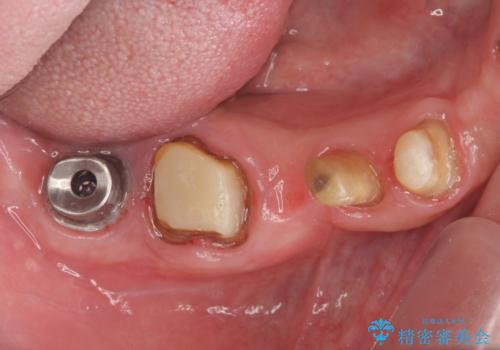

- 「歯がぐらぐらして噛めない、歯を抜いて欲しい、またしっかりと噛めるようになりたい。」、と歯周病治療を希望され来院されました。

歯の根本まで骨吸収が進み、ぐらぐらになってしまった歯を抜去し骨の造成を行ったのちインプラント治療を計画します。